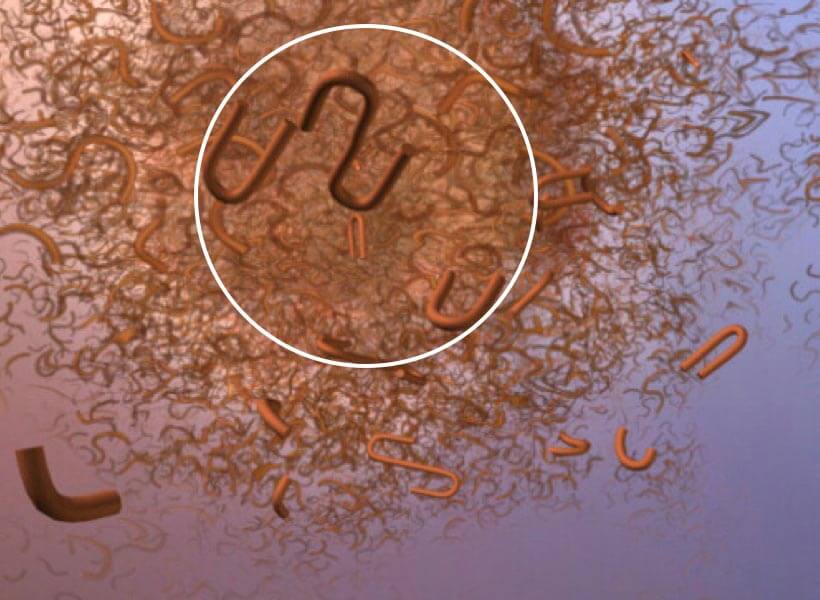

More About Plaques

Plaques form when protein pieces called beta-amyloid (BAY-tuh AM-uh-loyd) clump together. Beta-amyloid comes from a larger protein found in the fatty membrane surrounding nerve cells.

Beta-amyloid is chemically "sticky" and gradually builds up into plaques.

The most damaging form of beta-amyloid may be groups of a few pieces rather than the plaques themselves. The small clumps may block cell-to-cell signaling at synapses. They may also activate immune system cells that trigger inflammation and devour disabled cells.